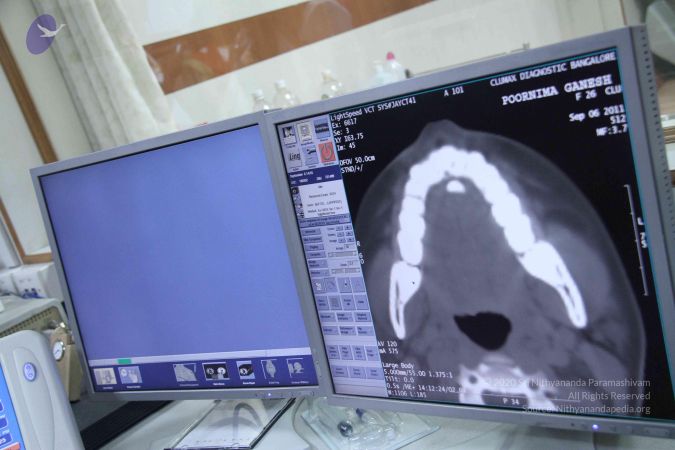

Scientific Validation of Materialization The most significant in a series of studies conducted by the research team were the tests done on Poornima (Ma Nithya Mahayogananda), a young entrepreneur and Paramahamsa Nithyananda’s energy channel from Singapore. On 6th September 2011, three different studies were conducted during a 4-hour session, in which Paramahamsa Nithyananda materialized a variety of objects through this individual, including sacred ash and precious stones. The studies were: 1) Whole body baseline CT scan of the subject Baseline whole-body CT scans proved the absence of any hidden objects in the body and vicinity of the subject. After the energy transfer from Paramahamsa Nithyananda to the subject, a repeat scan clearly shows the sudden appearance of a radio-opaque foreign body in the oral cavity without any delay or repositioning. The recording of the spiral CT after materialization revealed the presence of materialized objects both in sections and 3D format. 2) Simultaneous qEEG of Paramahamsa Nithyananda and the subject The qEEG recording of both Paramahamsa Nithyananda and the subject done during the process of energy transfer clearly showed ‘Entrainment’ (Synchronicity) in the brain waves of both individuals during the process of materialization, proving that a process of attunement was indeed taking place at the time